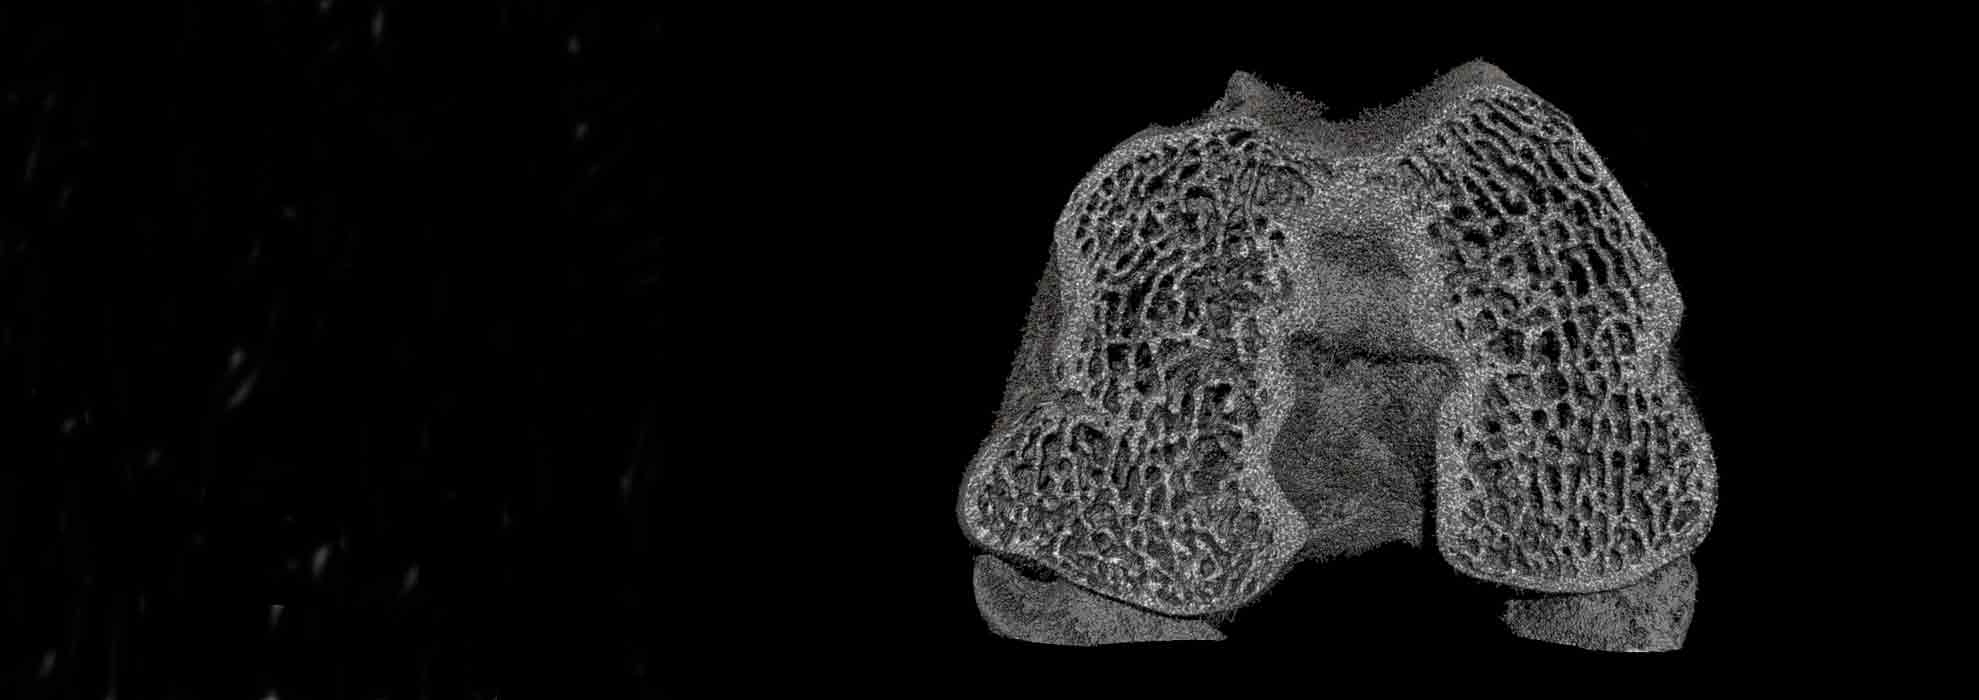

La evaluación y reconstrucción 3D de escáneres microtomográficos nos permite ampliar los resultados obtenidos, tanto de las características de tejidos y materiales como de su interacción.Más información

Podemos completar los estudios con la microtomografía, que nos aporta datos de la microestructura y densidad ósea y de su interacción con los materiales.